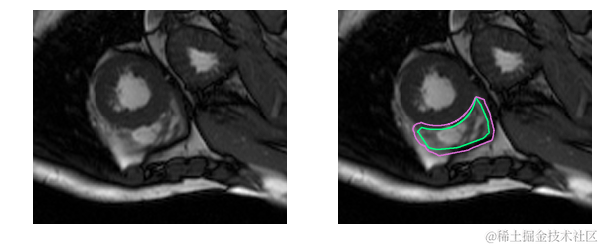

这是一个分割起来很容易的例子。这一个比较困难:

而这对于没有经过训练的眼睛来说完全是一个挑战: